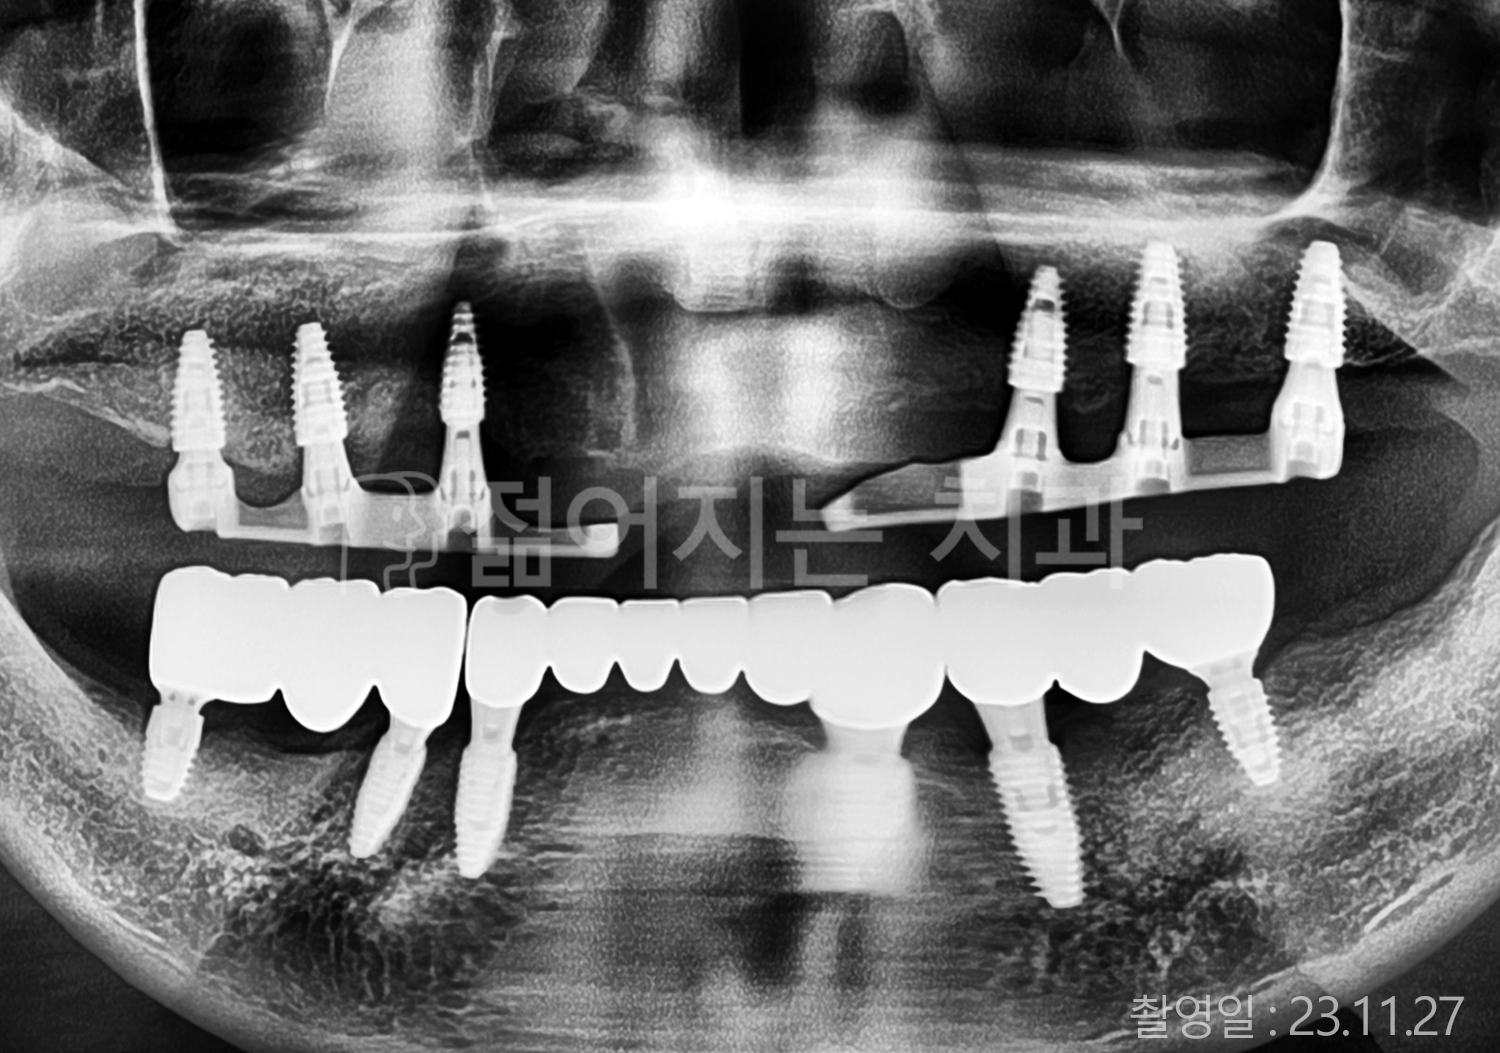

• 40대 전체치아 10개 이상 임플란트

• 50대 전체치아 10개 이상 임플란트

• 50대 고혈압, 당뇨, 고지혈증 전체치아 10개 이상 임플란트